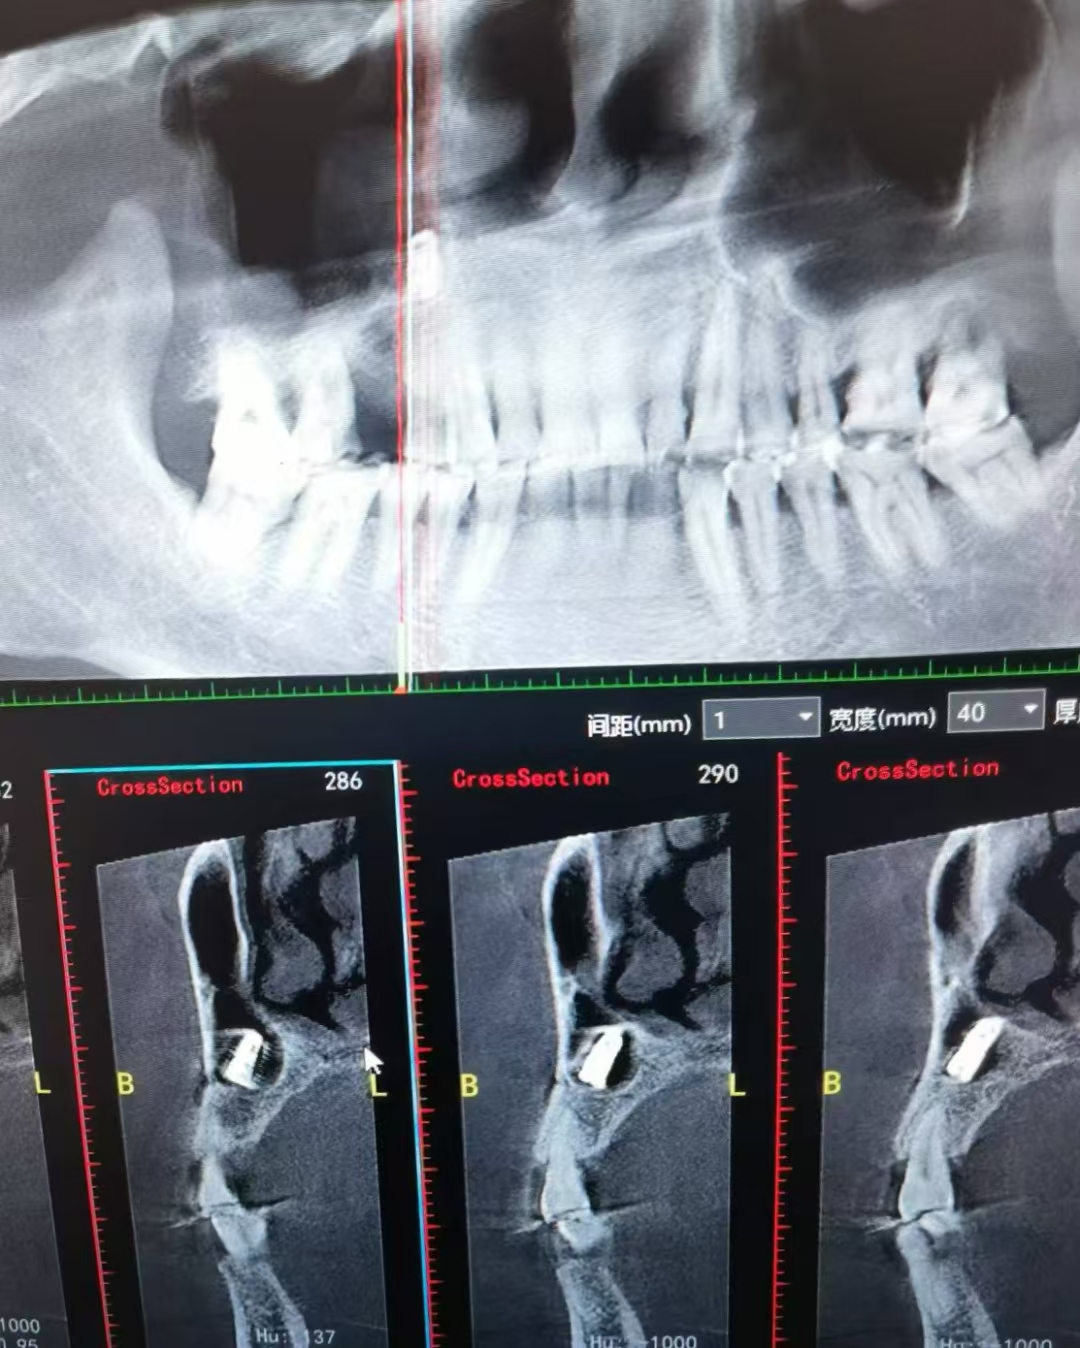

植体掉入上颌窦取出